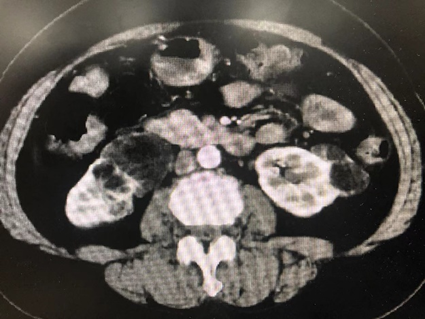

病例五,52岁女性,发现右肾肿物1月。CTU提示右肾癌7.7cm×6.8cm×11.6cm,伴MayoII级下腔静脉癌栓,长6.5cm。既往乙肝肝硬化。贫血。行机器人辅助腹腔镜右肾根治+下腔静脉瘤栓取出术,术者:张洪宪教授。术中发现肿瘤生长迅速,瘤栓较术前3天的影像学检查相比有进展,术中探查发现瘤栓已生长至下腔静脉肝后段,且质地极为糟脆,由于肝后下腔静脉不容易进行近心端阻断,遂采用不阻断近心端方法:充分游离肝后下腔静脉后,术中切开下腔静脉,采用“Milk”技术,用纱布沿下腔静脉近心端将下腔静脉瘤栓向下全部挤压出下腔静脉管腔,之后用纱布压迫下腔静脉近心端做临时阻断,同时缝合下腔静脉壁。